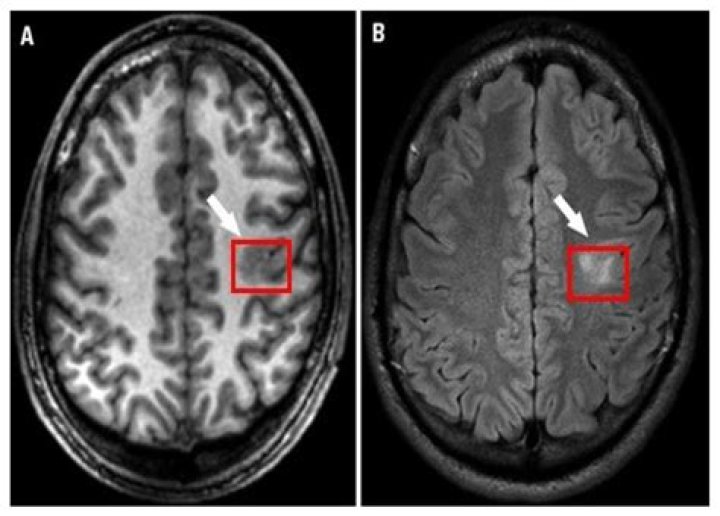

Vestibular schwannoma is one of the common benign tumors that arise from the vestibulocochlear nerve. It is termed intralabyrinthine schwannoma (ILS) when the tumor is originated from the Schwann cells surrounding the terminal branch of the vestibulocochlear nerve inside the membranous labyrinth (1, 2).

Cochlear schwannomas are rare benign neoplasms which arise in the cerebellopontine angle, internal auditory canal, or within the cochlea. These tumors are typically slow growing especially when they reside within the otic capsule.

intralabyrinthine schwannomas. Schwannoma is a benign neoplasm of the nerve sheath and is the most common neoplasm of the IAC and CPA. “Acoustic” schwannomas most often arise from the vestibular division of the vestibulocochlear nerve.

Schwannoma is a benign neoplasm of the nerve sheath and is the most common neoplasm of the IAC and CPA. “Acoustic” schwannomas most often arise from the vestibular division of the vestibulocochlear nerve. These tumors arise from the perineural Schwann cells surrounding the vestibular and cochlear nerves.